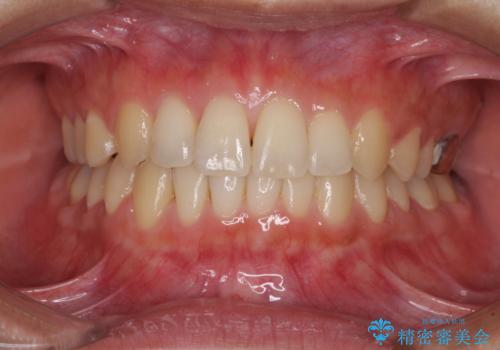

- 1年6ヶ月

- 10-30回

- 治療費の目安: 75万円費用は治療当時の料金となります